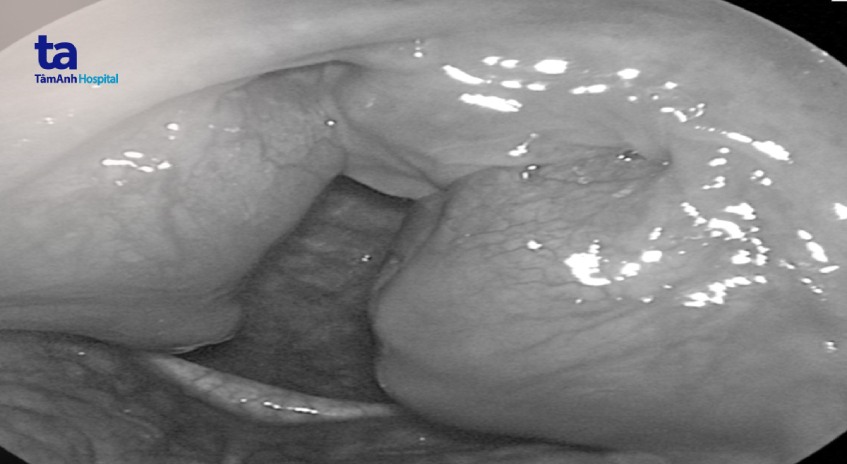

Khối amidan kích thước 4cmx4cm, to gấp đôi bình thường che lấp gần hết đường thở, gây ra chứng ngưng thở khi ngủ và tiếng “ngáy sấm” hằng đêm ở nam thanh niên.

Thăm khám tại Bệnh viện Đa khoa Tâm Anh, ThS.BS.CKI Nguyễn Thị Hương, khoa Tai Mũi Họng, phát hiện anh Bảo bị viêm amidan quá phát độ 4 (mức độ nặng nhất), gây ngưng thở khi ngủ, cần phải phẫu thuật cắt bỏ ngay.

Amidan quá to, che lấp gần như toàn bộ vùng họng khiến bác sĩ gặp khó khăn khi thao tác. “Phẫu trường khá chật chội để thao tác nên khó thực hiện hơn các ca thông thường. Tuy vậy, nhờ sử dụng công nghệ coblator hiện đại và kinh nghiệm của ekip nên cuộc mổ diễn ra suôn sẻ trong 30 phút. Công nghệ Coblator có ưu điểm vừa cắt nên hạn chế mất máu. Thêm nữa, loại dao này sử dụng nhiệt độ thấp nên ít gây đau và tổn thương vùng xung quanh”, bác sĩ Hương cho biết.